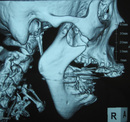

顎関節症の診断方法と治療法の選択肢

診断方法には、問診や視診のほか、X線やMRI、CTスキャンなどの画像診断が用いられます。治療法としては以下が挙げられます: